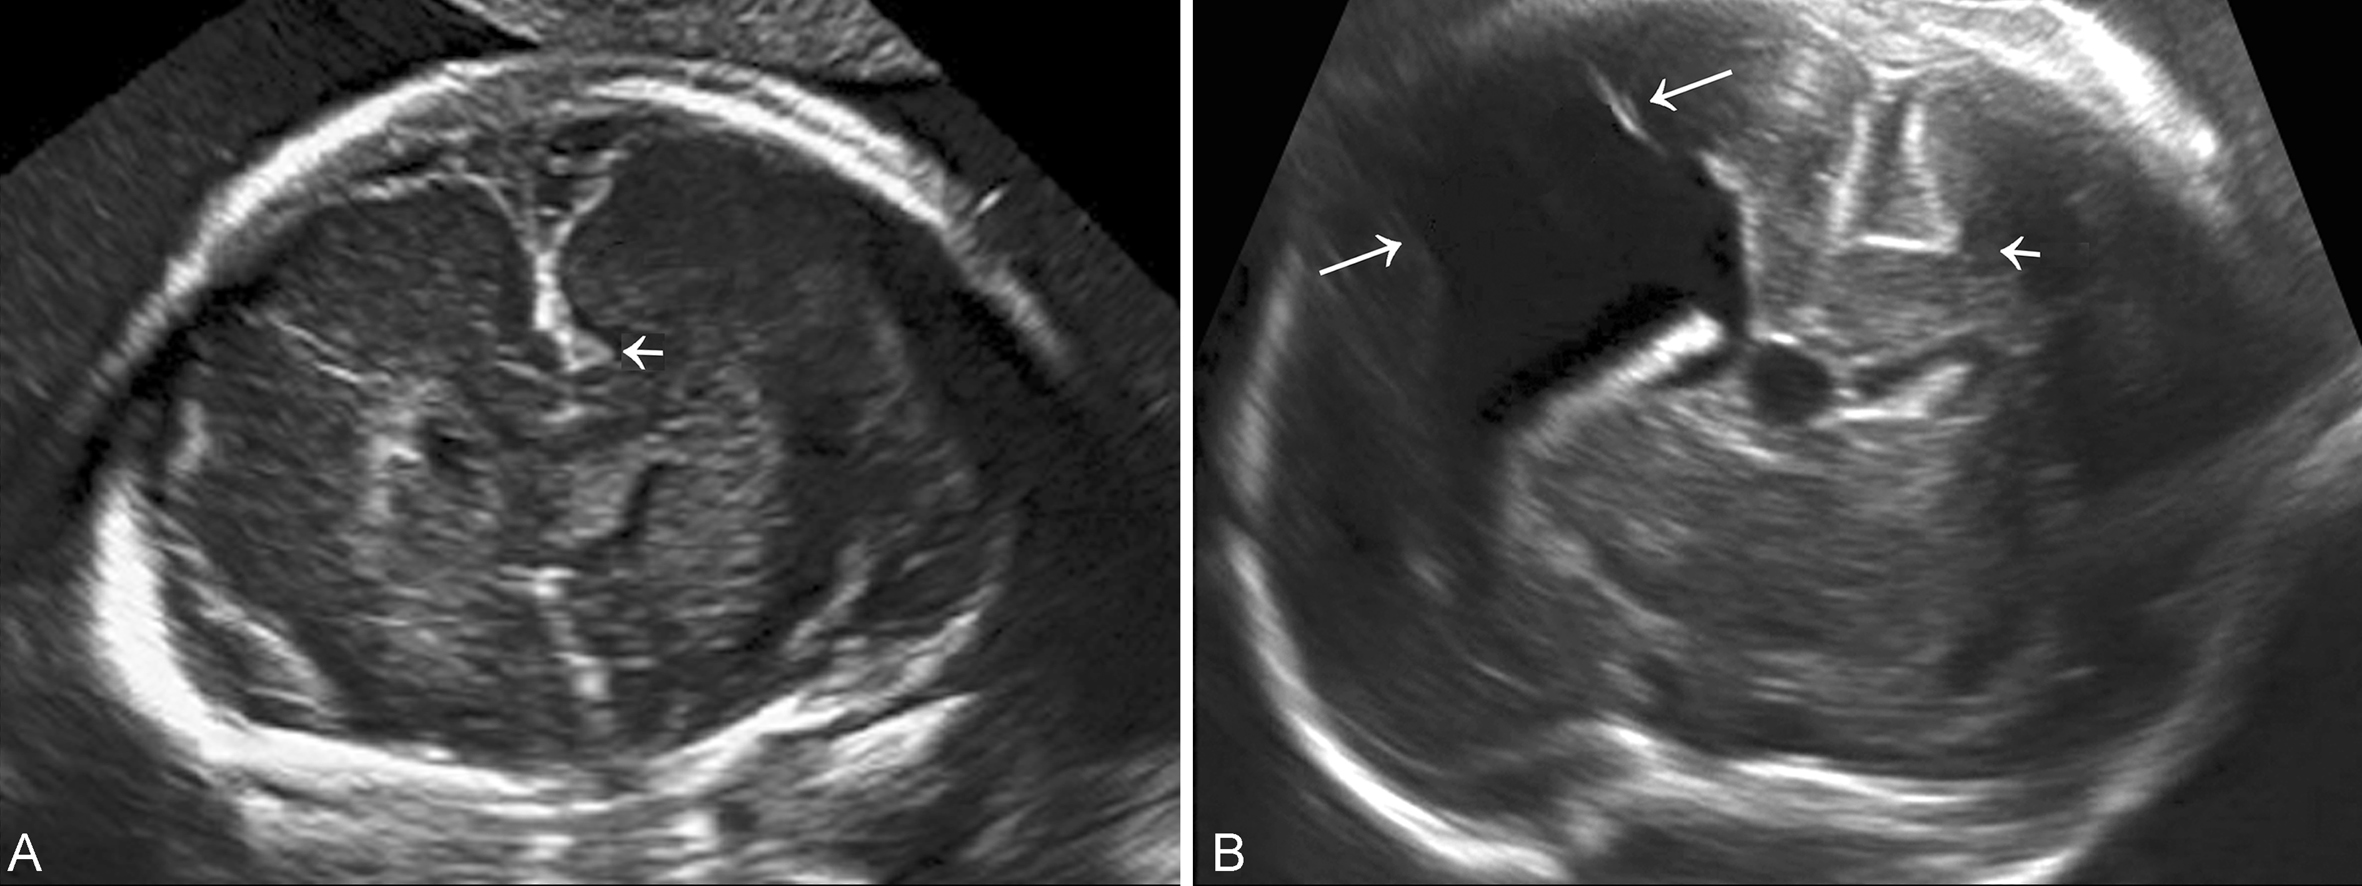

Ⅰ型超声容易漏诊,有时仅显示为脑实质内带状强回声(图1)。小的Ⅱ型脑裂畸形不仔细观察也容易漏诊,超声特有的“混响”伪像使得小裂隙模糊不清晰而漏诊。典型的Ⅱ型脑裂畸形表现为充满脑脊液的从大脑表面到脑室系统的裂隙(图2),裂开处的无回声与侧脑室相通,或者与蛛网膜下腔相通。裂开的表面有灰质覆盖,回声较强。可对称也可非对称,单侧或者双侧裂开。脑裂发生的部位不同,对颅内组织结构的影响不同,受影响的结构常常有透明隔不显示、脑室扩张、多小脑回畸形、胼胝体缺失等。三维超声检查可以通过连续的断面和三维重建追踪显示裂隙的走形和连接关系,有利于对Ⅱ型脑裂畸形的诊断。

图1脑裂畸形(A:Ⅰ型脑裂畸形;B:Ⅰ、Ⅱ型脑裂畸形共存)